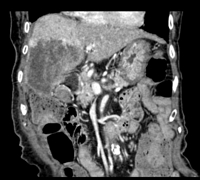

オリンパスの最新鋭内視鏡システム(EVIS LUCERA ELITE)での胃内視鏡、大腸内視鏡、経鼻胃内視鏡(鼻から挿入する内視鏡)による観察(NBI観察も可能)と早期癌・ポリープ切除などの処置を行っています。また全例コンピューターでの録画を行い、検査後に録画映像にて詳細な説明を行います。さらにコンピューターファイリングシステムによる迅速な診断を行っております。